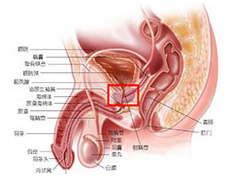

前列腺增生是“谁”引起的?

前列腺增生是谁引起的?前列腺增生疾病,是一种男性到了 中老年时期 容易发生的疾病。伴随着年龄的增长,疾病的发病率也呈上升趋势。前列腺增生严重危害着患者的身体。老年人...[详细]

【前列腺增生】

【前列腺增生】